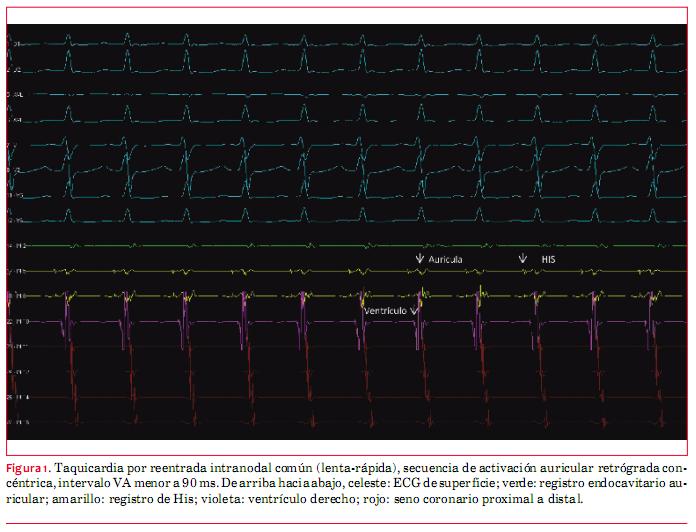

Se avanzó un catéter cuadripolar con visualización directa a través del sistema de navegación, realizando reconstrucción de vena cava inferior; el registro de electrogramas auriculares evidencian el ingreso a las cavidades cardíacas (figura 1).

Utilizando en el navegador las proyecciones oblicua anterior derecha (OAD) y oblicua anterior izquierda (OAI) y con la guía de los registros endocavitarios, se posicionan electrodos cuadripolares en ápex de ventrículo derecho y cara lateral de aurícula derecha, octopolar en la región del His, y catéter decapolar en el seno coronario desde subclavia izquierda. Posicionados los cuatro catéteres diagnósticos, se procedió a realizar estudio electrofisiológico. Se confirma que el mecanismo de la arritmia es una reentrada nodal común (doble fisiología nodal, taquicardia inducible luego de prolongación crítica del intervalo AH, secuencia de activación auricular retrógrada concéntrica con intervalo VA menor a 90 ms, y extrasístoles ventriculares con His refractario no reciclan la taquicardia) (figura 2).